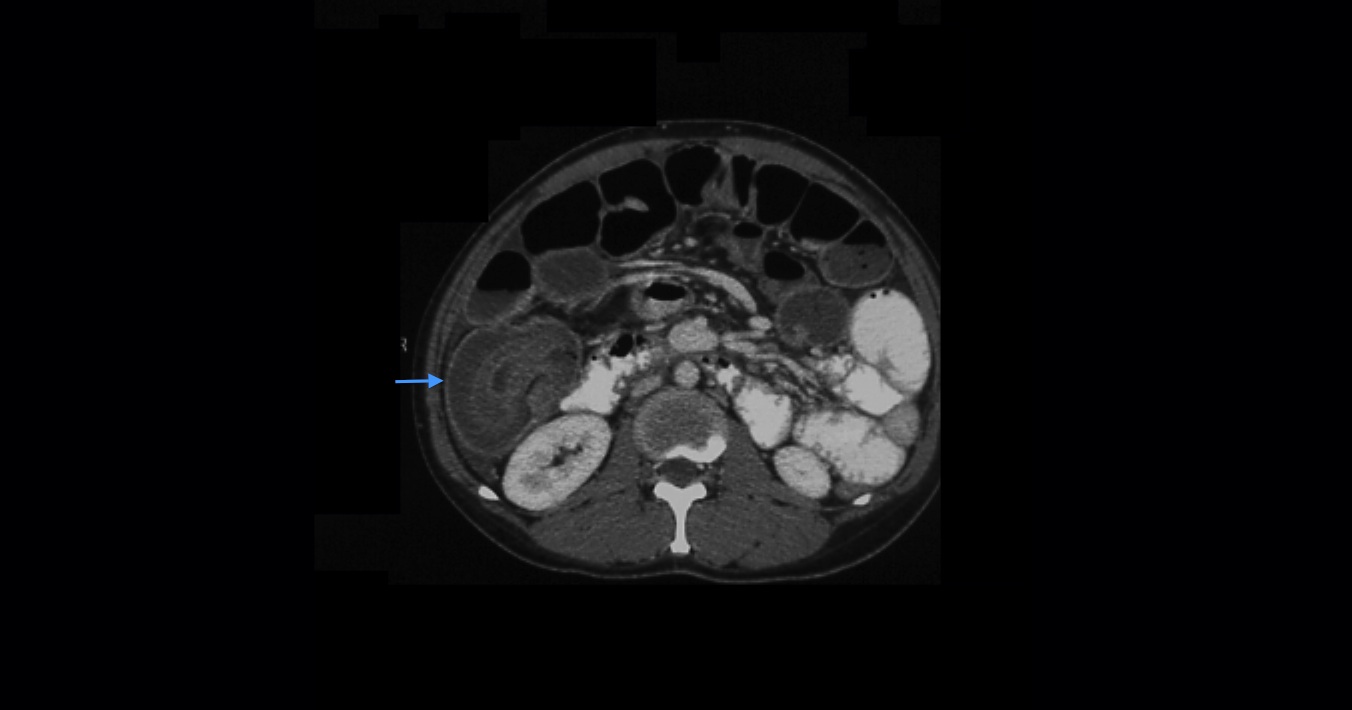

Small bowel obstruction is a common clinical presentation that presents a diagnostic conundrum. Over the last 2 decades, there has been a paradigm shift in the radiological investigation of small bowel obstruction (SBO) and in the indication for and timing of surgical intervention. Cross sectional imaging (predominantly computed tomography) has largely replaced the widespread use of radiographic small bowel follow-through studies as the imaging modality of choice for SBO. This article illustrates the current imaging modalities available for diagnosis of small bowel obstruction. (Full text available online at www.medpharm.tandfonline.com/ojfp) S Afr Fam Pract 2015; DOI: /10.1080/20786190.2014.977052